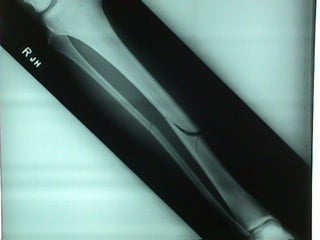

• Long Bones- metacarples,

metatarsals, phelangies, humerus,

ulna, radius, tibia, fibula

Humerus

Ulna

Radius

Tibia

Fibula